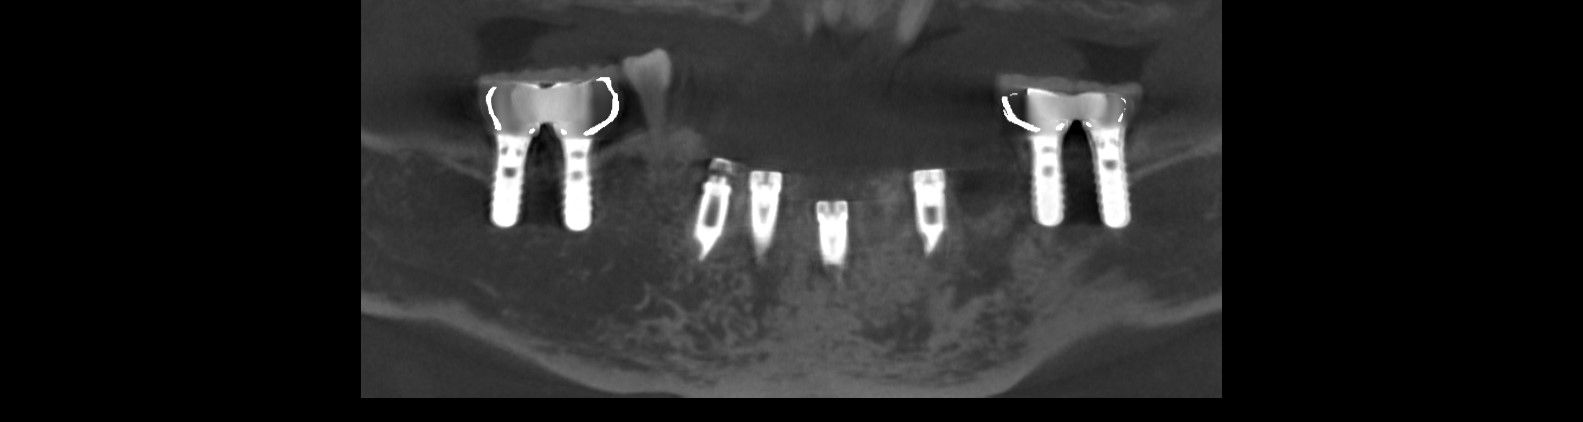

先日インプラントの型取をした患者さんの被せ物が出来上がってきました。

これをネジを使ってインプラントに接続します。